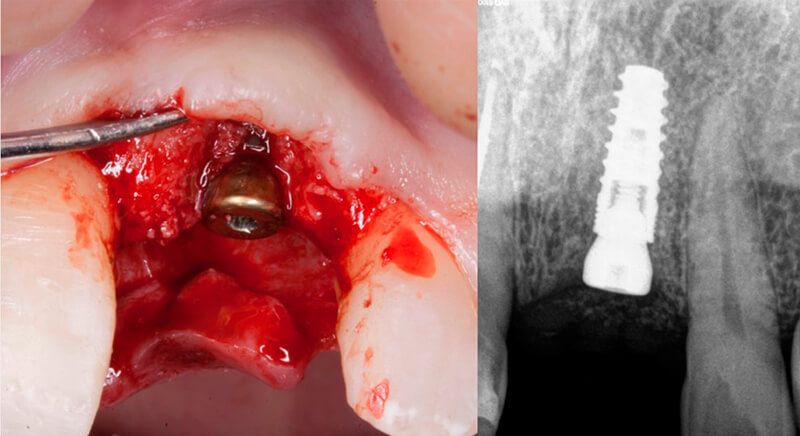

The guided surgery was performed by lifting a full thickness mucoperiosteal flap. A Biomimetic Ocean CC implant, diameter 3.5mm and length 10mm, was inserted using the surgical guide in the ideal three-dimensional position and the defects were regenerated with xenograft and reabsorbable membrane, the nasopalatine duct on the palatine side and the area of dehiscence on the vestibular.

During the same surgical intervention, a short 3mm Avinent healing abutment was positioned and fully covered by the flap. Primary closure was completed and we waited 6 months for the bone graft to mature.